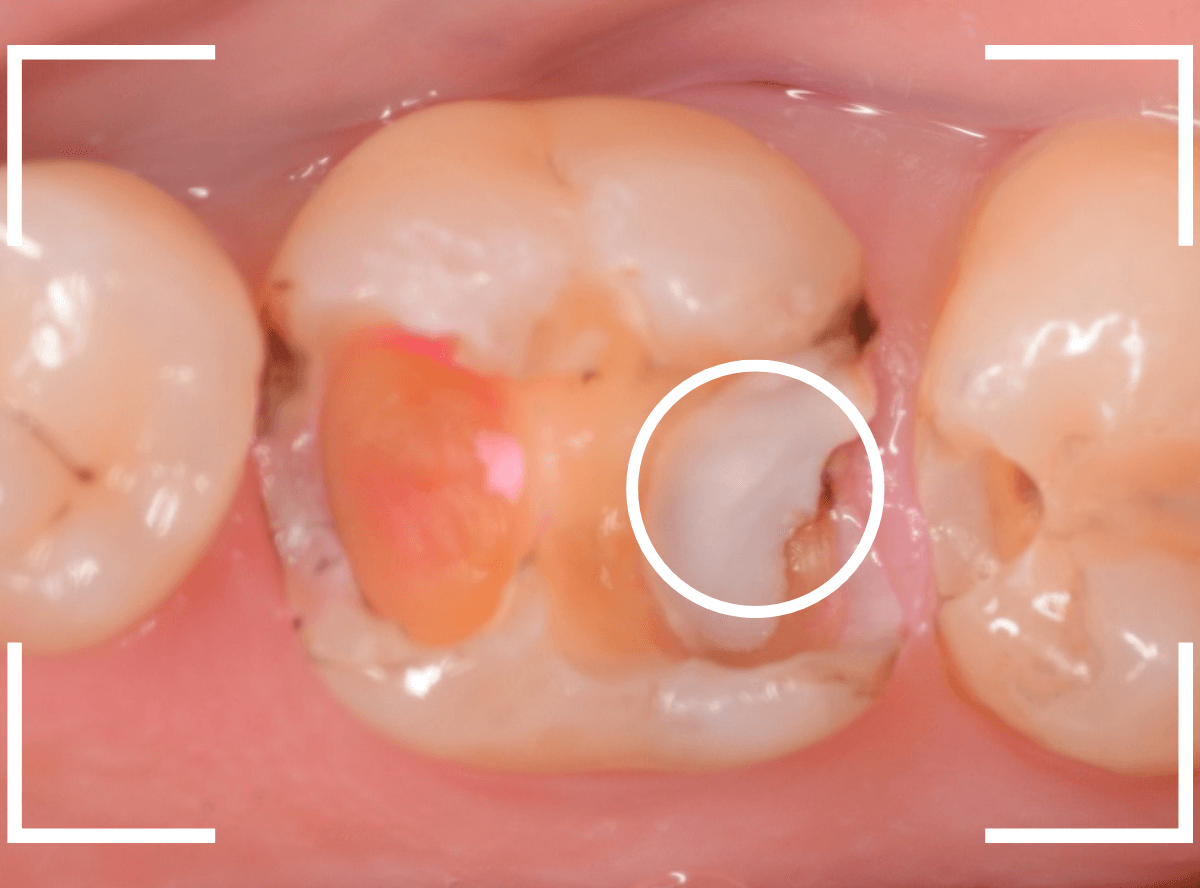

Case.19 メタル・クラウン、除去・再治療後、オール・ジルコニア・クラウンへ 4

今回は、上の奥歯の銀歯(メタル・クラウン)の中で虫歯になってしまった方です。

通常は、さし歯の中が虫歯になってしまうと、レントゲンにも写らず見つけづらいのですが・・・。

歯を裏側から見たところです。

幸い、見える部分に虫歯が

さし歯と歯肉の間に虫歯ができているのがわかります。

歯の奥まで虫歯が進んでいるのか、浅い虫歯ですんでいるのかは治療をしながら調べていく必要があります。